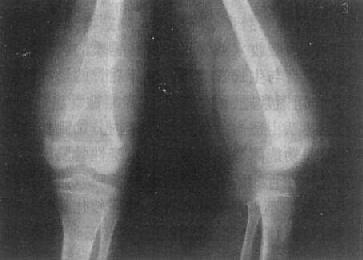

图2-1-4 正常成人膝关节

股骨下端和胫骨上端的骨性关节整齐,间隙清晰,宽度均匀